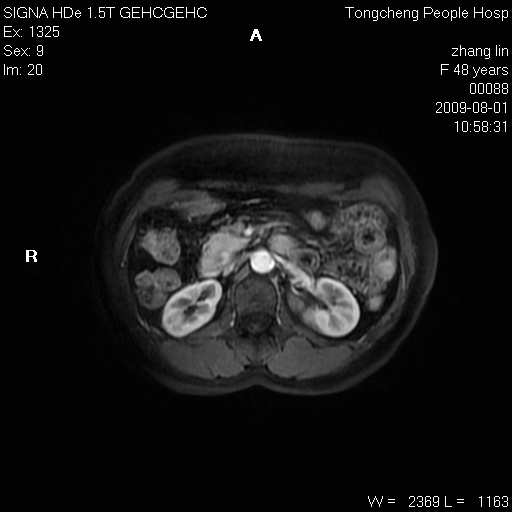

女,48岁。健康体检,彩超发现右肾占位性病变。平素健康。

临床诊断:右肾占位性病变,性质待定(囊肿?肿瘤?)。

上中腹部mr平扫+增强扫描,图像如下:

右肾上极见一类圆形病灶,t1wi呈等信号t2wi呈等高混杂信号,三期增强无强化,边界清---考虑囊肿出血。

同反相位均表现为等信号,病变无强化,考虑含蛋白的囊肿可能,弥散加权相或许有些帮助,

慢性胆囊炎